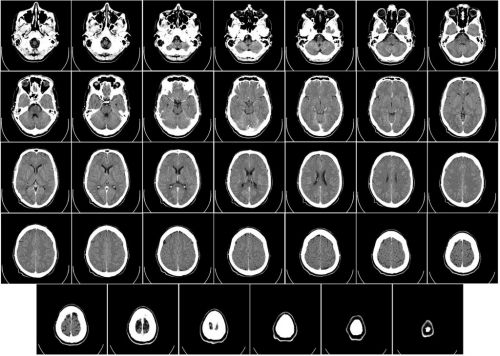

Любая томография – это пошаговое сканирование участков тела человека для создания трехмерных черно-белых изображений. Но принципы работы МРТ и КТ отличаются, поскольку в их основе – разные физические явления.

Томография - это послойное исследование органа или части тела человека pixabay.com